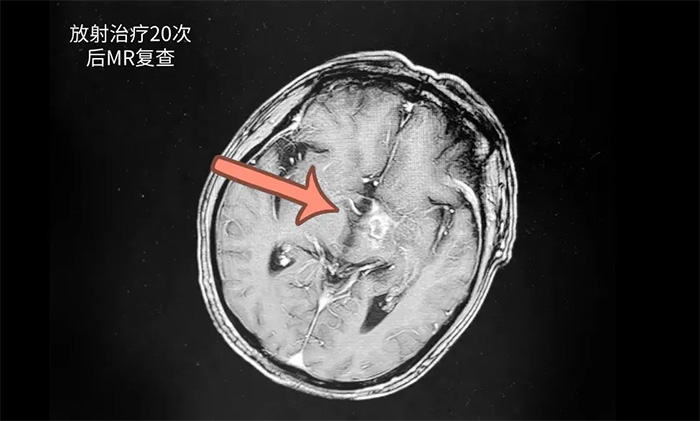

王晓东主任团队为患者完善各项检查。根据患者的临床资料、病理诊断和影像结果,明确患者满足放疗条件,并制定了完善周密的放疗计划。为患者开展20次放射治疗。历时约1个月完成治疗后,患者头晕、头痛,伴言语不清等症状有了不同程度改善。复查头颅MR,可见病灶范围明显缩小。

▲ 复查显示病灶范围明显缩小